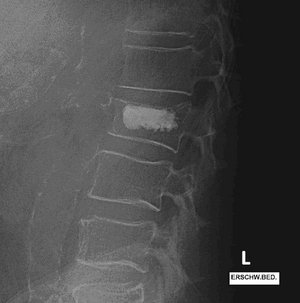

Röntgenbild der Lendenwirbelsäule zeigt Wirbelkörper und Bandscheiben deutlich.

Osteoporotisch bedingte LWK 2-Fraktur

Röntgenbild der Lendenwirbelsäule mit Wirbelkörperfraktur und Kyphoplastie.

Stabilisierung des Wirbelkörpers mittels Kyphoplastie LWK 2

Frakturbehandlung bei osteoporotisch bedingten Frakturen der Wirbelsäule

Bei einer vorliegenden Osteoporose treten neben ausgeprägten Schmerzen gehäuft Frakturen im Bereich der Wirbelsäule auf.

Minimalinvasive Stabilisierung durch Kyphoplastie

Bei den häufig stabilen Frakturen mit Einbrüchen im Bereich der Deck- und Grundplatte der Wirbelkörper ist eine operative Versorgung oft durch eine minimalinvasive Stabilisierung der Wirbelkörper durch eine sogenannte Kyphoplastie als eine komplikationsarme und schonende Operation möglich.